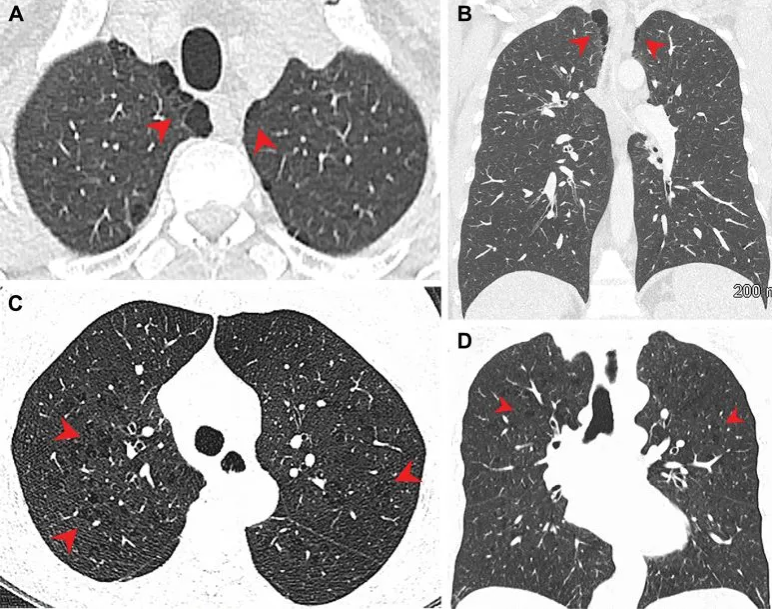

Plicní emfyzém u (A, B) marihuany a (C, D) kuřáků tabáku. (A) Axiální a (B) koronální CT snímky u 44letého muže kuřáka marihuany ukazují paraseptální emfyzém (šipky) v bilaterálních horních lalocích. (C) Axiální a (D) koronální CT snímky u 66leté kuřačky tabáku s centrilobulárním emfyzémem reprezentovaným oblastmi centrilobulární lucence (šipky). Kredit: Radiologická společnost Severní Ameriky